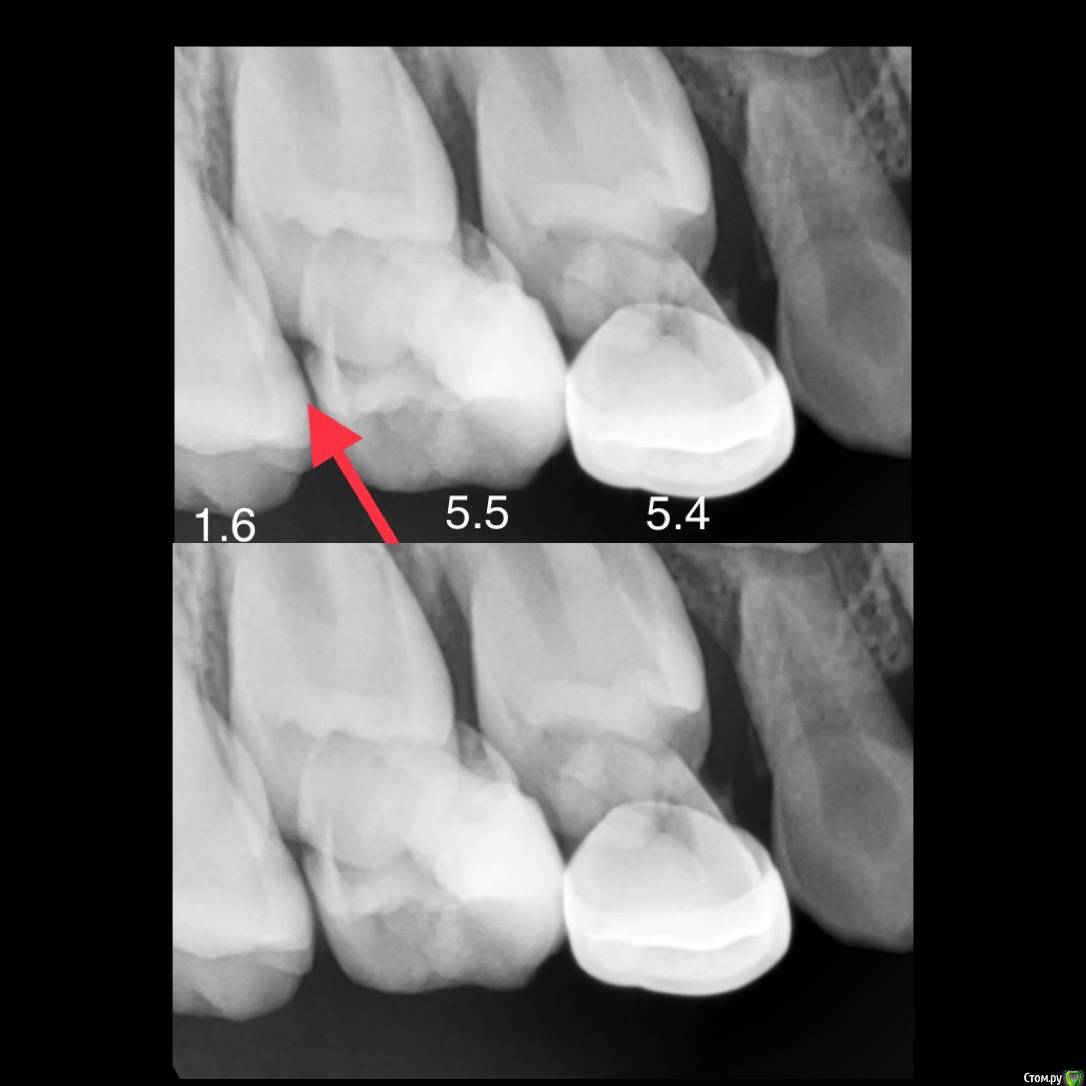

CRAZYDUCK Опубликовано 31 мая, 2018 Автор Поделиться Опубликовано 31 мая, 2018 (изменено) Просто гипоплазия , осложнённая кариесом 4.6 зуба . Поражены все 6 зубы (3.6 и 2.6 в большой степени , 3.6 нужно покрыть коронкой ;/ ) 4.6 и 1.6 в небольшой степени . Кариес маркер для родителей ( для наглядности ).Зато 1.6 эктопирован и «сожрал» корень 5.5. Ещё не исправляли эктопию. Выложить снимки эктопированного 1,6 ? Изменено 31 мая, 2018 пользователем CRAZYDUCK 2 Ссылка на комментарий